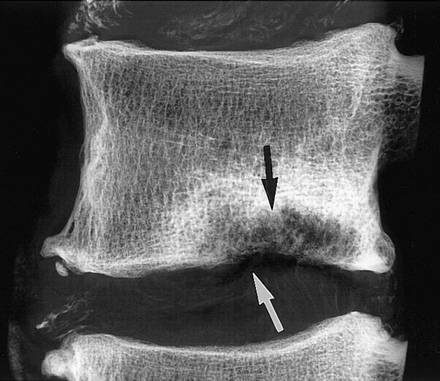

Грыжа Шморля поясничного отдела позвоночника представляет собой «проваливание» хрящевой замыкательной пластинки, расположенной между позвонком и межпозвонковым диском, в тело одного из пяти поясничных позвонков. На рентгенограмме позвоночного столба выглядит как каплеобразное вдавление темного на снимке диска в светлый прямоугольник выше или ниже лежащего позвонка.

При выставлении диагноза используется несколько определяющих признаков по результатам рентгенологической, КТ или МРТ-диагностики.